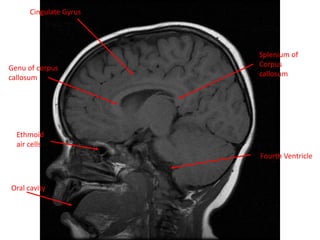

Cingulate Gyrus

Genu of corpus

callosum

Ethmoid

air cells

Oral cavity

Splenium of

Corpus

Fourth Ventricle